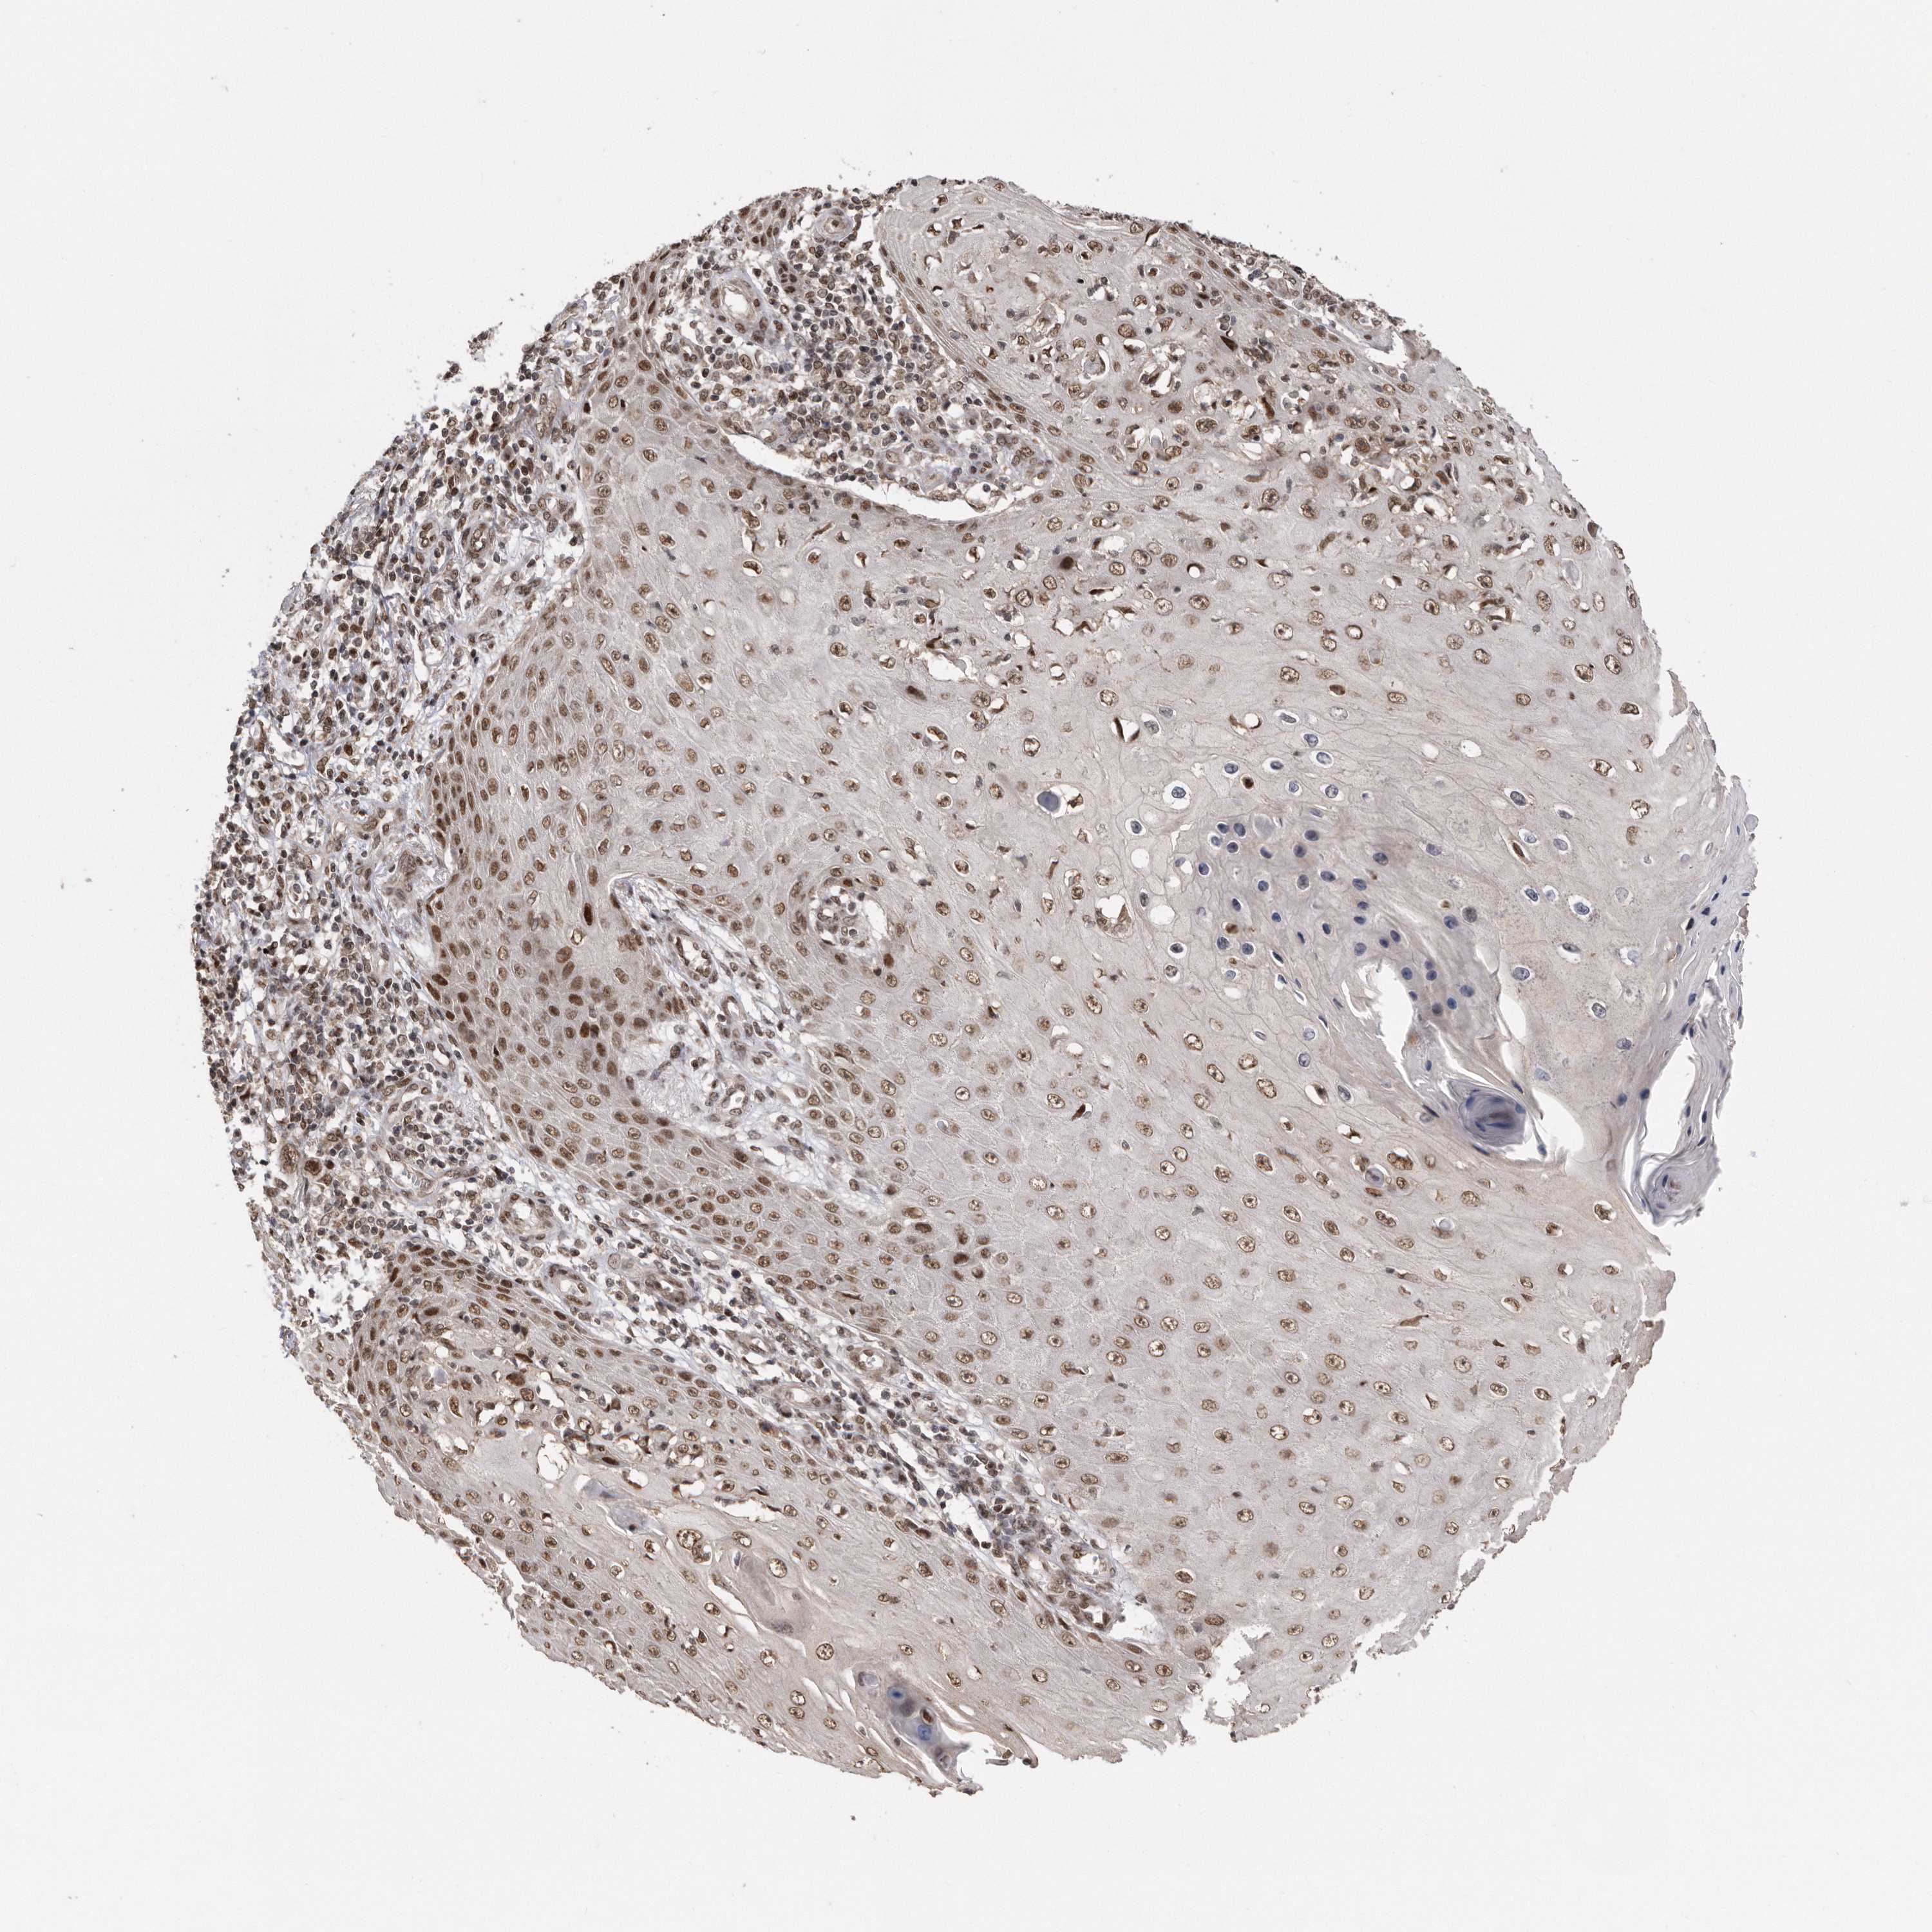

Basal cell and squamous cell cancer

SKIN CANCER - Protein expressioni

A mouse-over function shows sample information and annotation data. Click on an image to view it in a full screen mode. Samples can be filtered based on level of antibody staining by selecting one or several of the following categories: high, medium, low and not detected. The assay and annotation is described here.

Antibody stainingi

Antibody staining in the annotated cell types in the current human tissue is reported as not detected, low, medium, or high, based on conventional immunohistochemistry profiling in selected tissues. This score is based on the combination of the staining intensity and fraction of stained cells.

Each image is clickable and will lead to virtual microscopy that enables deeper exploration of all samples and also displays staining intensity scores, fraction scores and subcellular localization as well as patient and tissue information for each sample.

Antibody CAB034925

Staining

High

Intensity

Strong

Quantity

>75%

Location

Nuclear

Squamous cell carcinoma, NOS